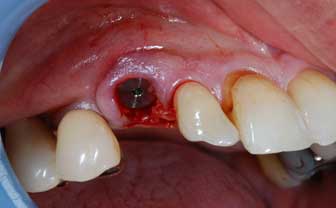

IMPIANTI POST-ESTRATTIVI

Impianto post-estrattivo

In un paziente cardiopatico di 72 anni